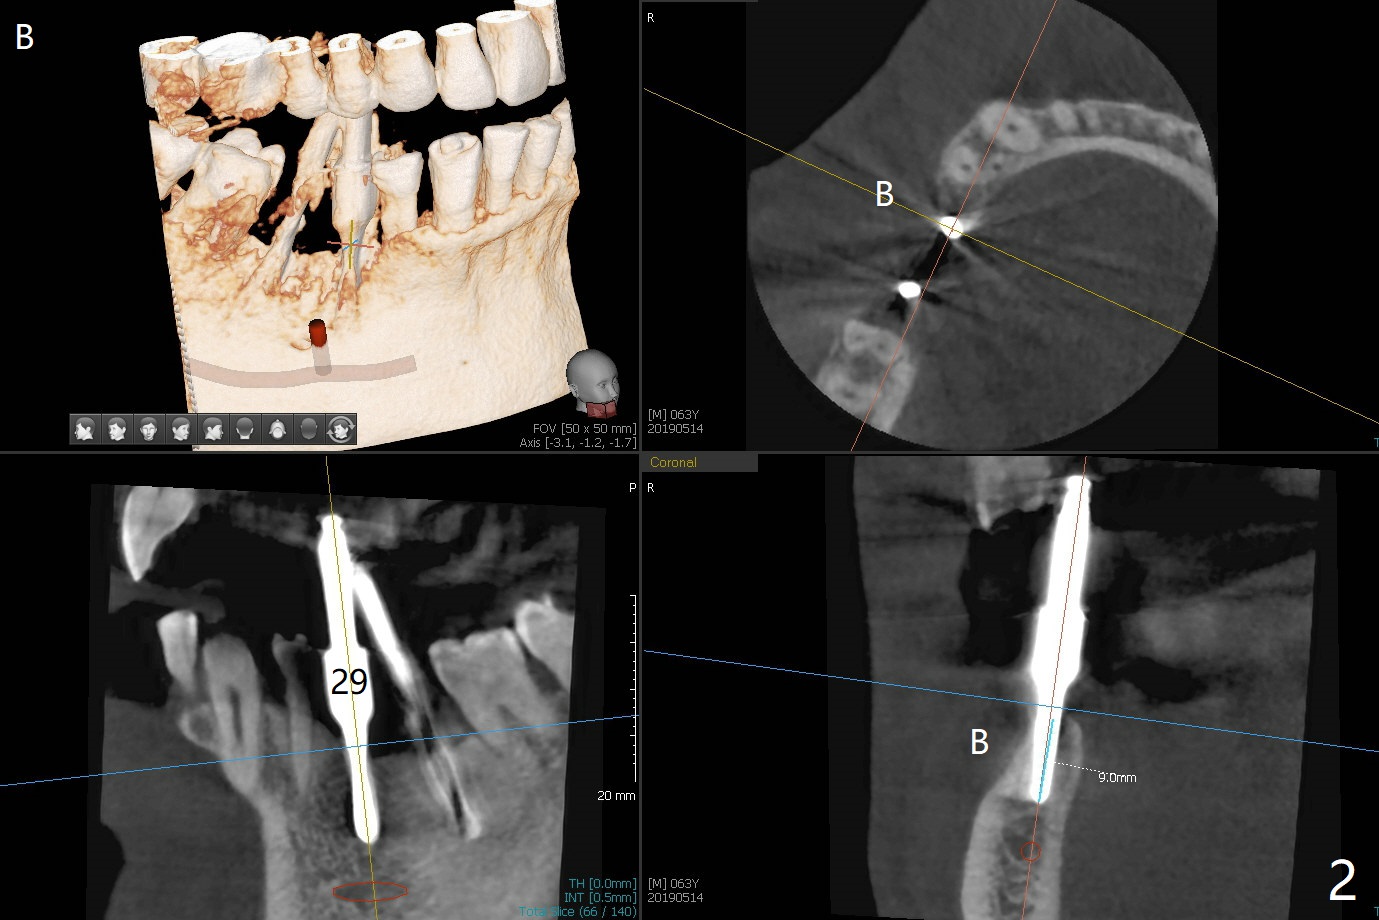

After initial osteotomy using 2.2 mm drill for 10 and 11.5 mm at #29 and 30, respectively, the guide is removed for re-insertion of drills and PA (Fig.1). The osteotomy at #29 is found lingually and in the nonkeratinized gingiva with mild laceration (wish incision to be made before osteotomy); the osteotomy is established a little lingual at #29 (Fig.2) and more or less in the middle of the narrow ridge and #30 (Fig.3). Lindamann bur is used to move #29 osteotomy buccally. A 1.5 mm drill is used to increase the depth free hand before placement of 2.5x10(4) mm 1-piece implants (Fig.4). After adjustment of the implant depth (Fig.5), CT is retaken, which shows proper implant placement (Fig.6,7). Probably due to good oral hygiene, the gingiva around the implants appears to be keratinized 4 months postop (Fig.8). After abutment preparation for margin and parallelism, impression is taken (Fig.9). When the permanent crowns are temporarily cemented, the large gingival embrasure is noted (Fig.10,11). The latter could be reduced by modifying the provisional in the healing stage. In fact the crown at #29 dislodges 2 days post cementation because lingual (Fig.12) and distal (Fig.13) placement. A surgical stent should have been fabricated from RPD for free hand placement!